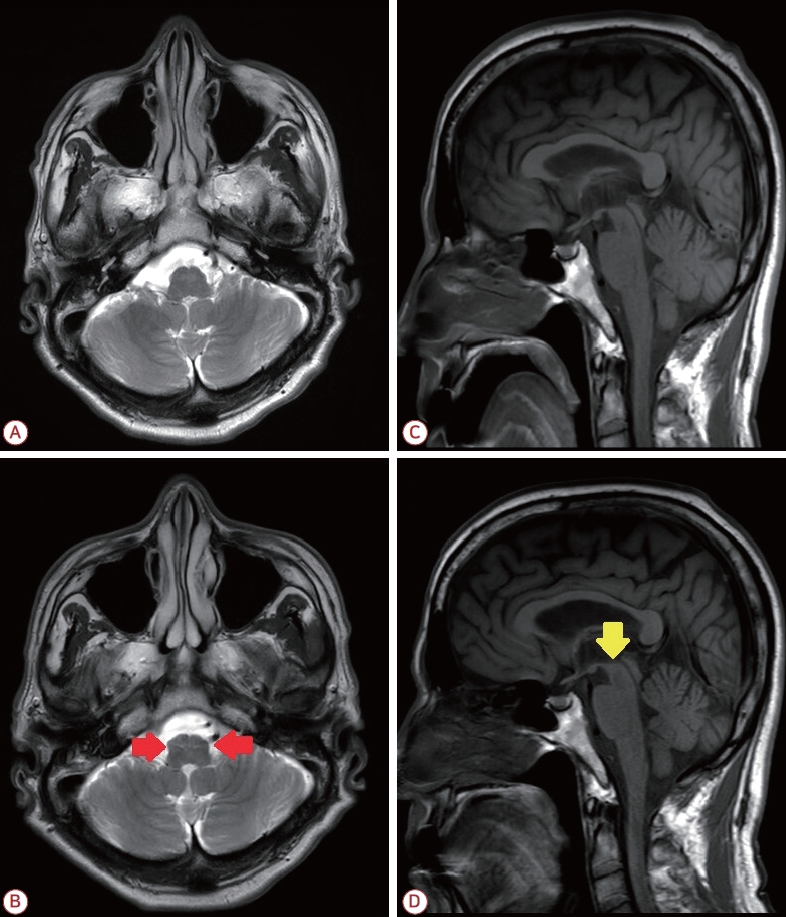

뇌자기공명영상에서는 6년 전 어지럼증이 있어 시행한 영상과 비교하여 T2강조영상에서 양측 아래올리브핵(inferior olivary nuclei)의 고신호 및 비대화가 새로 관찰되었고(Fig. A, B) 시상(sagittal) T1강조영상에서 중뇌 위축이 진행되어 위 윤곽이 평평함이 확인되었다(Fig. C, D). 18F- fluoropropylcar bomethoxyiodophenylnortropane (18F-FP-CIT) 양전자방출단층촬영(positron emission tomography, PET)에서 양측 조가비핵(putamen)의 도파민운반체 섭취 저하가 좌측에서 더 두드러졌다. 레보도파-카비도파복합제인 퍼킨(perkin)을 100 mg/25 mg 하루 3회 투약을 시작하였으나 증상의 호전은 없었고 입천장떨림 역시 지속되었다. UPDRS 운동척도 점수는 17점으로 치료 전후 변화가 없었다.

Brain magnetic resonance imaging (MRI) findings of the patient. (A, C) Axial T2-weighted and sagittal T1-weighted MRIs obtained 6 years earlier. (B) Axial T2-weighted MRI demonstrates newly developed symmetrical hyperintensity and hypertrophy of the bilateral inferior olivary nuclei (red arrows, hypertrophic olivary degeneration) compared to (A). (D) Sagittal T1-weighted MRI shows interval progression of midbrain atrophy with flattening of the superior midbrain contour (yellow arrow, hummingbird sign) compared to (C).